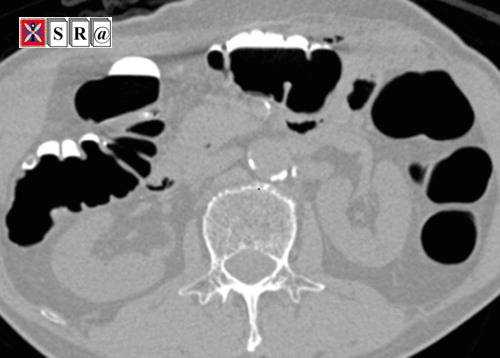

Introduction: Colorectal cancer, as one of the most important fatal cancers, is caused by the lack of timely diagnosis of colorectal polyps. Presently, because of the advancements in CT imaging of the colorectal device, the CTC-CAD is a promising method for the duly diagnosis of these appendages. In this regard, Electronic Colon Cleansing (ECC) is one of the effective factors that enhance diagnostic accuracy in the methods used in CTC-CAD. To date, various methods have been utilized for ECC (e.g., the mosaic decomposition (MD) method) that each has advantages and limitations. Therefore, the aim of this study is to combine the methods of linear computing of previous studies and also some image processing methods to improve the quality of electronic cleansing of data on residual materials that existed in CT colorectal images. This proposed method is called LM_ECC.

Given the death rate of 57,000 per year due to colon cancer in the United States and recent advances in colorectal imaging by Computerized Tomography (CT) technology, the CT Colonography (CTC) is known a tool for detecting intestinal cancer. CTC is a CT imaging from the abdominal cavity, which is done to detect colorectal polyps. CTC images are utilized in computer-aided diagnostic systems. CTC-CADs consist of three main parts: patient preparation before imaging, standard imaging, and soft computing on images for diagnosis. All diagnostic techniques of CTC-CADs require those images that do not have confusing data because the remainder of the residual materials from the colon can be misinterpreted as a part of the colon. Therefore, it would result in increasing the false positives and subsequently reducing accuracy. Today, the electronic cleansing of colorectal CT images is considered a promising technique to remove the residual material in CTC images for the purification of the virtual cleansing after imaging.

The first and most basic solution proposed for identifying the confounding data is the thresholding method. The methods in this regard were introduced based on the use of statistical image features, vector quantization (in order to dimension reduction), image gradient information, and the classification of the Markov random field. Further methods have focused on using edge modeling during image categorization to effectively describe the labeled areas. Afterward, the image gradient was used in the later methods using a Sobel mask filtering. Then, more complex and effective algorithms with several carefully designed steps were proposed. These efficient methods utilize the effective features of the images and the combination of several highly accurate categorization methods. For this purpose, Cai et al. (2011) presented the mosaic decomposition (MD) method. According to the report, the sensitivity of 97.1%, the specificity of 85.3%, the accuracy of 94.7%, and AUC = 0.96 can be obtained in the classification of areas containing residual material, which are approximately good results for ECC.

The mentioned methods that utilized nonlinear computing such as the MD method have obtained relatively good results, but other methods can also be presented to improve the quality of electronic cleansing image using linear computing methods such as thresholding and solving its challenges. The aim of this study is to provide a combination of linear methods and some image processing methods in order to improve the quality of electronic cleansing of CTC images.